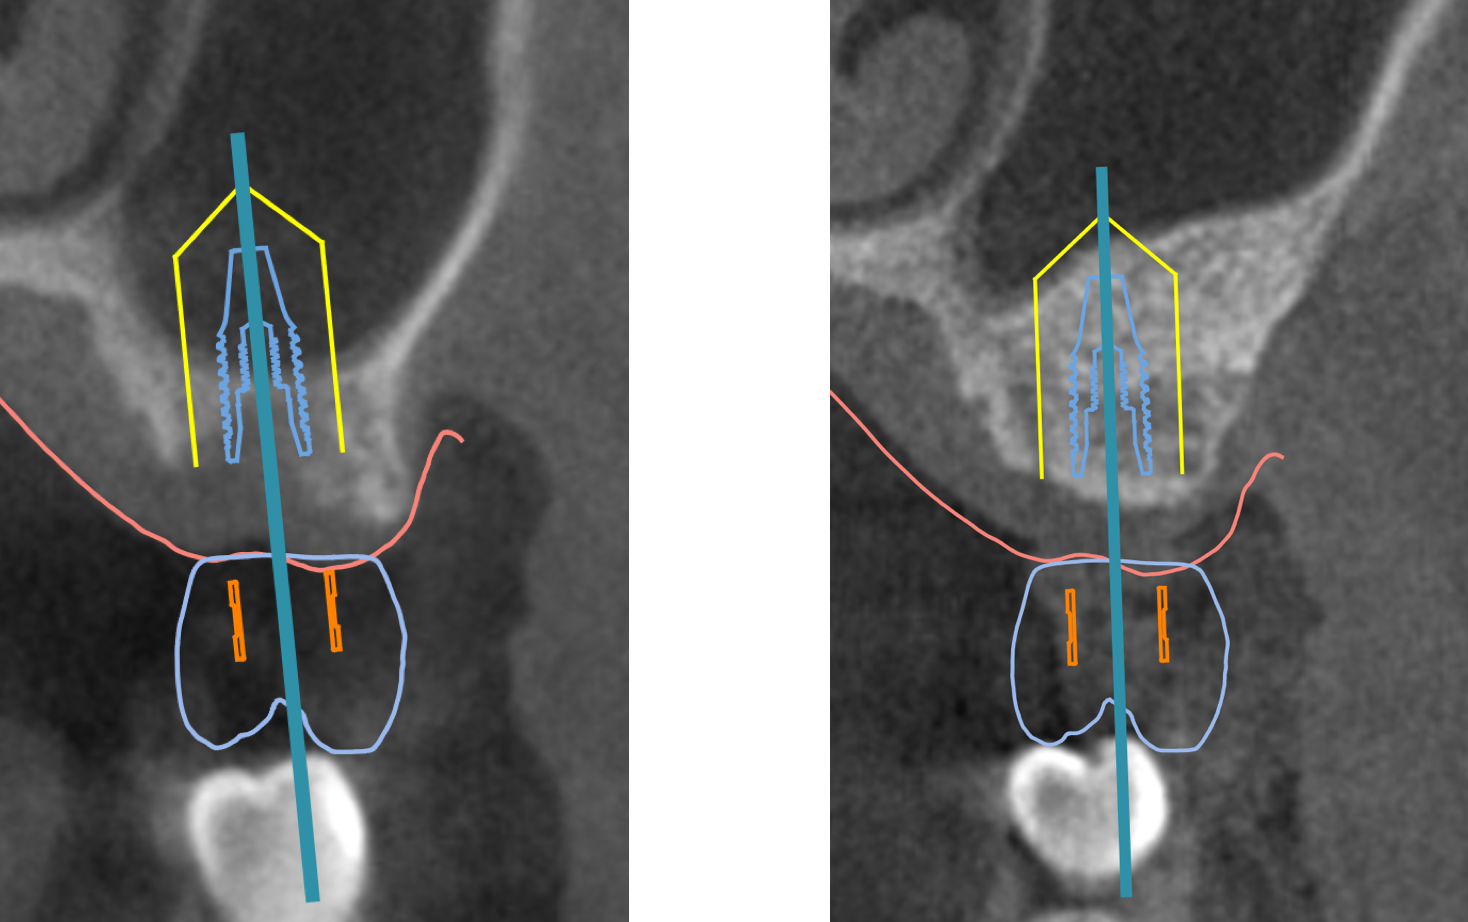

実際の症例

今回の患者様は、数本のご自身の歯に取り外し式の義歯(入れ歯)を装着された方でした

残念ながらご自身の歯は虫歯と歯周病が進行していたため、上下全ての歯を抜歯してインプラントを土台とした歯を作製していくこととなりました

今回の症例では、インプラントを埋め込んだ当日にインプラントを土台とした歯を装着することができましたので、その後は取り外し式の義歯を使用することがなく、患者様にも大変喜んでいただけました